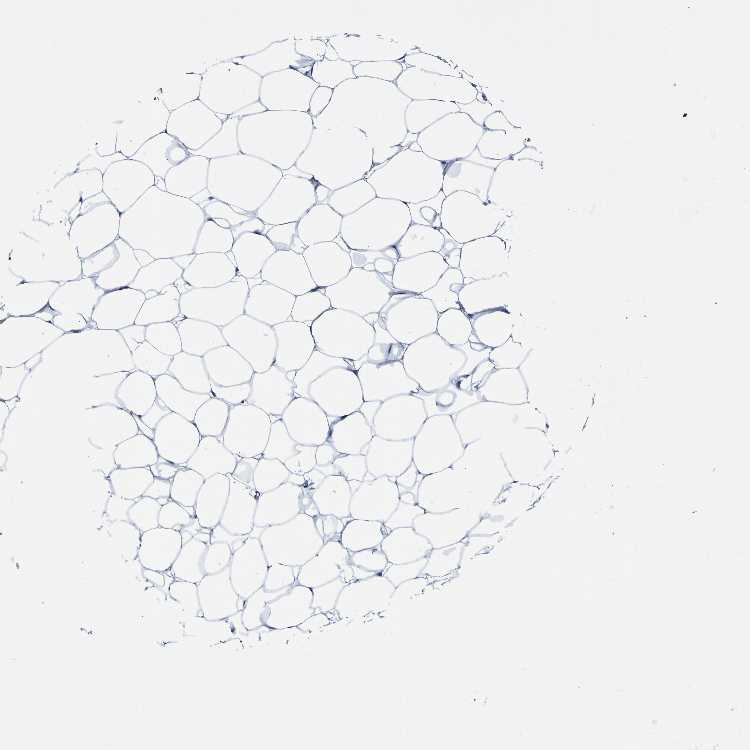

SOFT TISSUE 2 - Antibody stainingi

Antibody staining in the annotated cell types in the current human tissue is reported as not detected, low, medium, or high, based on conventional immunohistochemistry profiling in selected tissues. This score is based on the combination of the staining intensity and fraction of stained cells.

Each image is clickable and will lead to virtual microscopy that enables deeper exploration of all samples and also displays staining intensity scores, fraction scores and subcellular localization as well as patient and tissue information for each sample.

Antibody HPA011912

Fibroblasts Not detected

Peripheral nerve Not detected